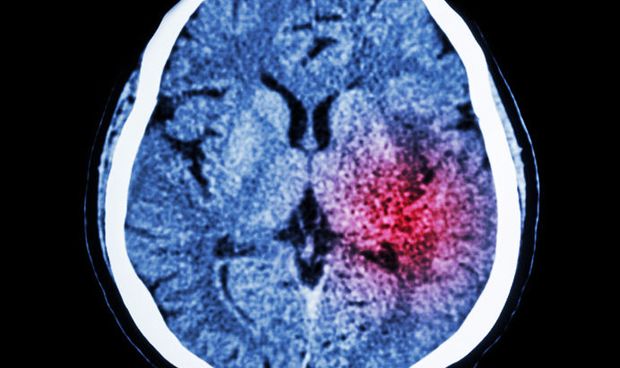

En el estudio se midió la inflamación cerebral utilizando un tipo de imagen cerebral llamada tomografía por emisión de positrones (PET). Las células inmunitarias del cerebro, conocidas como microglía, están involucradas en la respuesta inflamatoria normal del cerebro al trauma o la lesión, pero demasiada inflamación se asocia con otros trastornos degenerativos y depresión. Cuando se activan las microglías, producen más proteína translocadora (TSPO), un marcador de inflamación que se puede observar mediante imágenes PET.